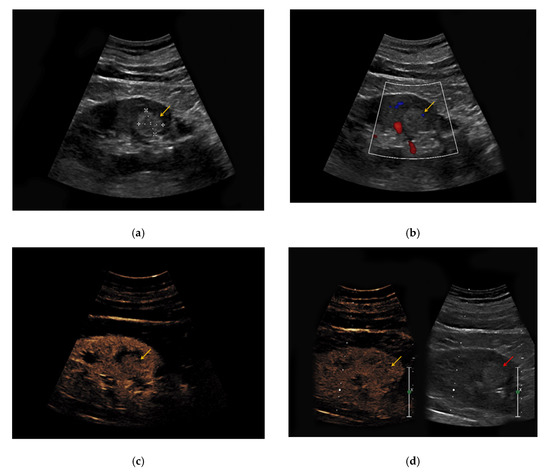

Figure 3. (a) Hyperechoic renal lesion with a diameter of 1.6 cm visualized in native B-mode (yellow arrow); (b) only slight vascularization was registered in Doppler mode (yellow arrow). (c,d) The lesion did not show hyperenhancement during the early (c, yellow arrow) and late phase (d, yellow arrow). Histopathological results showed a clear-cell renal cell carcinoma.

The heterogeneous sonomorphological features of the different histological subtypes of RCC are depicted in Supplementary Table S2. The majority of the CCRCC lesions presented as hypoechoic (33/47, 70%) compared to six hyperechoic lesions (13%) and five isoechoic lesions (11%). One lesion was iso-/hypoechoic (2%) and two lesions presented as hyper-/hypoechoic (4%). The PRCC lesions were hypoechoic in 27/42 cases (64%), hyperechoic in 8/42 cases (19%), and isoechoic in 5/42 cases (12%). One PRCC lesion could only be detected upon intravenous contrast application (2%) and one patient with bilateral PRCC presented with a hyperechoic lesion on the left and an isoechoic lesion on the right side (2%). Notably, 3/7 ChRCC lesions were hypoechoic (43%) compared to 4/7 isoechoic lesions (57%). Hypervascularization in Doppler Mode was detected in 7/47 CCRCC lesions (15%), in 2/42 PRCC lesions (5%), and 3/7 ChRCC lesions (43%). All 96 RCC lesions showed early enhancement upon application of contrast medium (Figure 3). Venous wash-out could be detected in 18/47 CCRCC lesions (38%), in 27/42 PRCC lesions (64%), and 6/7 ChRCC lesions (86%).